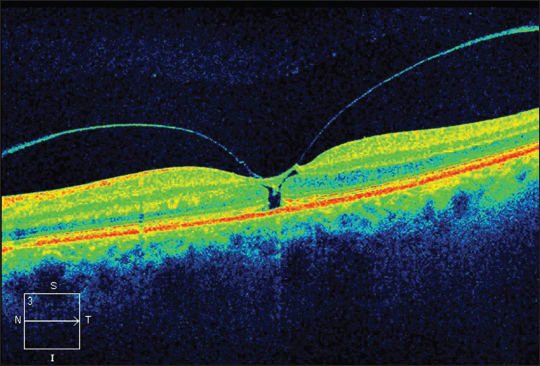

Optical coherence tomography has revolutionized our ability to visualize and examine the vitreomacular interface. This evolution has not only allowed clinicians to differentiate between the various pathologies more accurately, but it has also led to a better appreciation of the processes that are involved in creating these conditions. In turn, there has been a change in the paradigm of viewing the pathologies as separate entities toward recognition that they are all part of a spectrum, sharing the same pathological processes (Figures 7, 8, and 9).

Figure 9. SD-OCT of FTMH with LMH features of intraretinal split and ERM.